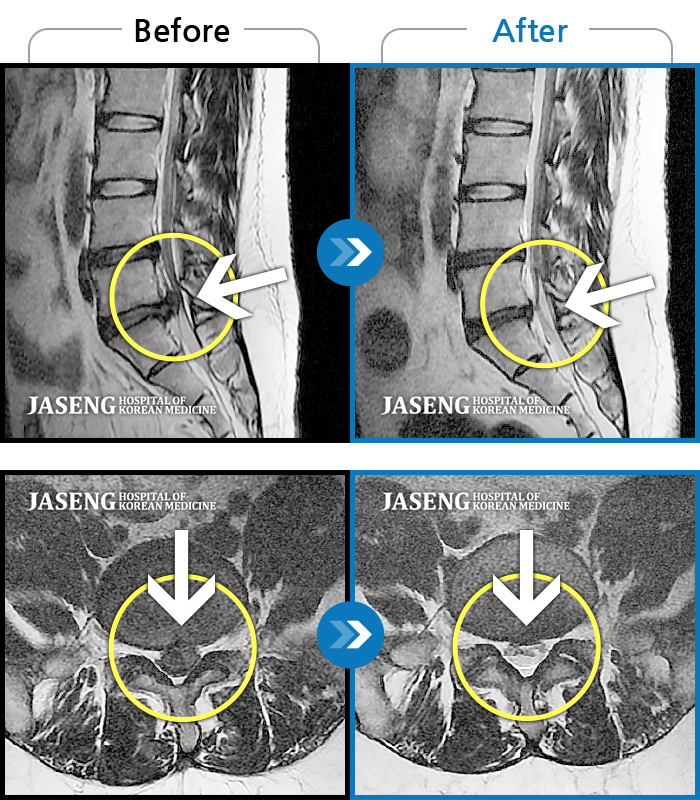

허리디스크로 일상생활이 힘들 정도로 고통을 겪던 시기에, 일산자생병원을 찾은 것은 제 인생에서 가장 잘한 선택 중 하나였습니다.

정확한 진단과 세심한 치료 덕분에 꾸준히 회복되었고, 지금은 예전처럼 편안하게 움직이고 생활할 수 있게 되었습니다.